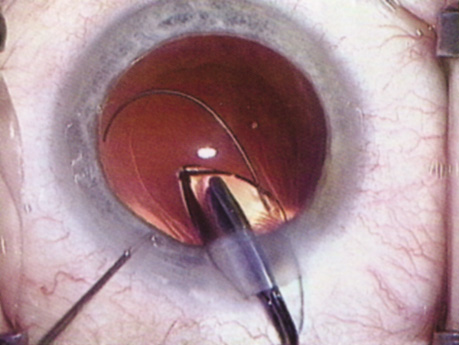

HYDRODISSECTION

Hydrodissection can be performed after the surgeon has successfully completed capsulorrhexis.97 If the capsulorrhexis is not intact, fluid forced around the interior of the capsule may cause the bag to splay open. With capsulorrhexis, hydrodissection is a safe and extremely useful maneuver. Hydrodissection can be thought of as two maneuvers: hydrodelineation and cortical cleaving hydrodissection. By placing a 27-gauge cannula on a syringe filled with balanced saline solution (BSS), the surgeon can direct fluid beneath the residual anterior capsular rim to create a cleavage plane. Depending on the direction the fluid wave takes, different lamellae of the cataract will be separated. Hydrodelineation is the term used when the cleavage plane separates the adult nucleus from the fetal nucleus or the adult nucleus from the more peripheral epinucleus. Hydrodelineation often results in the characteristic golden ring sign (Fig. 11). Cortical cleavage occurs when the cortex is separated from the capsular bag (Fig. 12). Finding the cortical cleavage plane may be facilitated by gently lifting the capsular margin away from the cortex with the BSS cannula before injecting. Several small bursts of fluid allow the surgeon to monitor progress of the fluid wave. When dealing with a soft nucleus, the authors strive to perform true cortical cleaving hydrodissection. For a hard nucleus, hydrodelineation allows manipulation of less of the nuclear bulk, although the remaining epinuclear shell must be addressed in an additional step. Hydrodelineation is particularly useful if the nucleus is not freely mobile after cortical cleaving hydrodissection.

Fig. 11. A crisp “golden ring” is seen from the fluid cleft between the epinucleus and nucleus with hydrodelineation.

Fig. 12. Hydrodissection, performed subincisionally with a 27-gauge J-cannula, produces a cleavage plane between the capsule and the cortex. The small blue arrows indicate the advancing fluid wave.